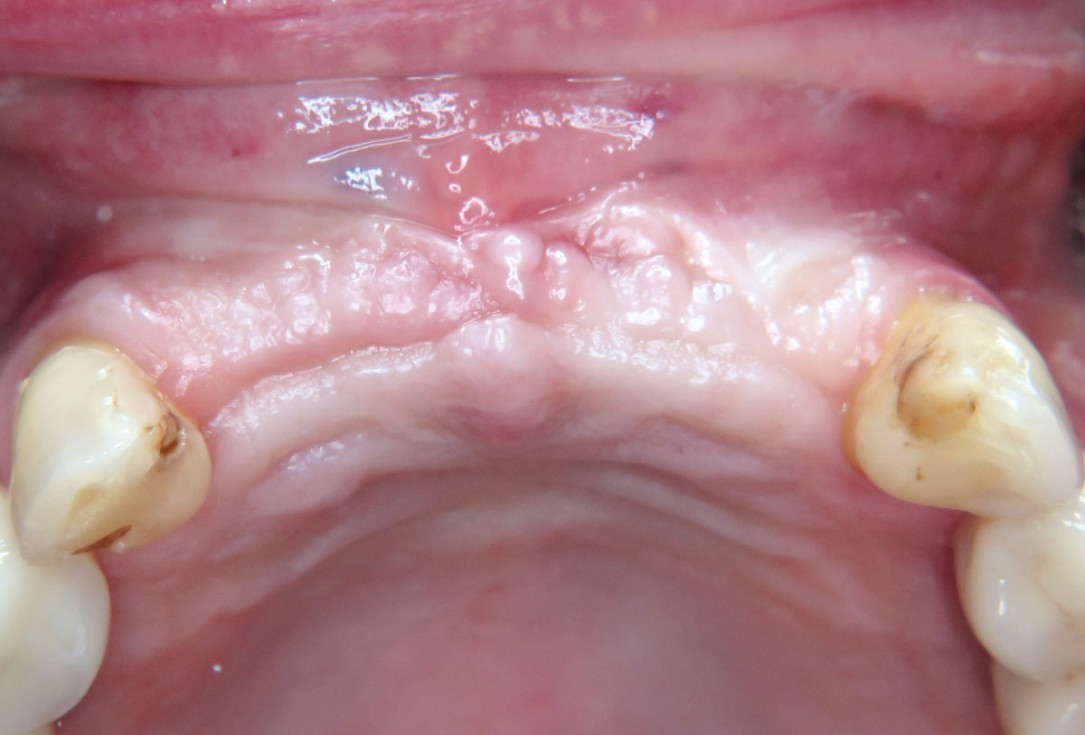

01 / 22 - Initial clinical situation – missing bonein regio 11, 12, 21, 22 and scarred soft tissue

Three-dimensional augmentation with maxgraft® cortico - M.Sc. E. Kapogianni